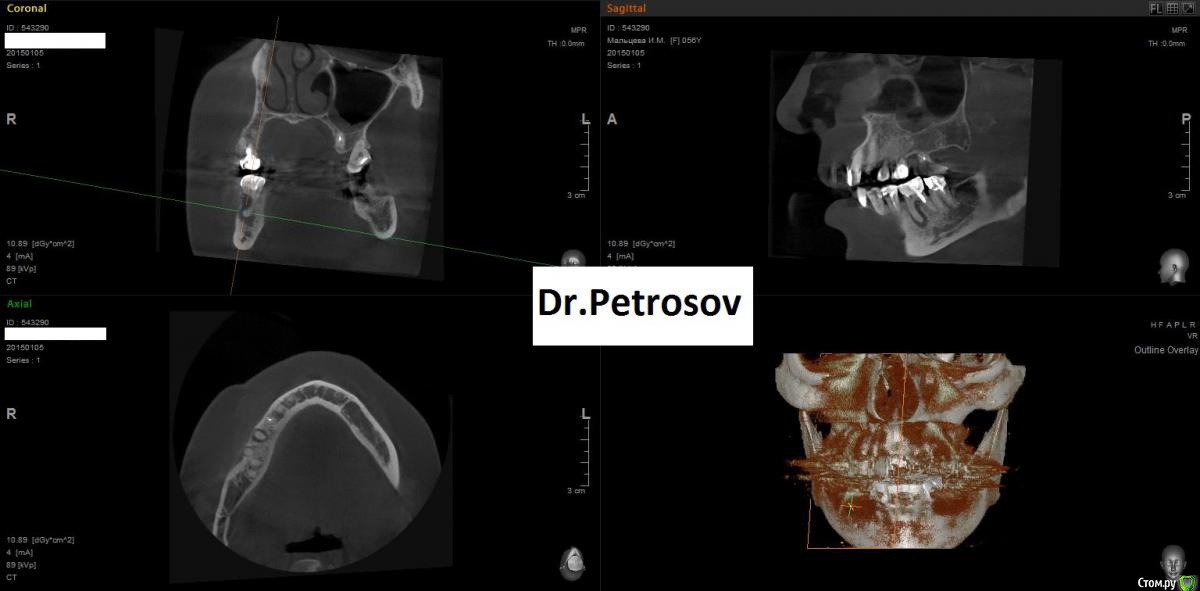

Dr.Feliks Опубликовано 11 февраля, 2015 Поделиться Опубликовано 11 февраля, 2015 Парнишка, мой сослуживец, пришел на плановый осмотр. В области зуба 3.7 увидал пародонтальный абсцесс у маргинального края десны. Со слов не беспокоит вообще, чувствует непонятный дискомфорт, но живет активной жизнью - не обращает внимание на мелочи)))Делаем КТ.На 3-м снимке результат лечения через 6 месяцев. Жду критики. Ссылка на комментарий

Dr.Feliks Опубликовано 11 февраля, 2015 Автор Поделиться Опубликовано 11 февраля, 2015 Опишите протокол инструментации/ирригации. Что чем до каких размеров на какую длину, чем и когда мыли и тд.8 ждет)Конечно хорошо бы и прицельный увидеть пол года назад. Или кт сейчас. Результат хороший.работа проведена без микроскопа и другой оптики. Коффер, Вскрытие полости зуба, расширение устьев ProtyperSx, ковер ручками до 20 на рабочую длину, затем Protyper S1,S2, ProFile 35/06, 25/06, 35/04 не доходя 1 мм до рабочей длины. Оставшийся 1 мм ручками 35 К. Ирригация: хлорка, эдта, вода, хлоргексидин + УЗ. Временное пломбирование Calasept на 2 недели. Свищ закрылся. После весь протокол ирригации и обтурация вертикалкой под СИЦ (3-й снимок с СИЦ пломбой) Ссылка на комментарий